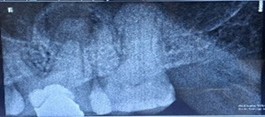

A 44-year-old woman presented to our dental department in May 2025 with a one-week history of a prominent left facial swelling extending from the corner of her mouth to the lower border of her left eyelid, accompanied by restricted eye opening. Her dental history was notable for a large amalgam restoration on tooth 26. Periapical radiography revealed an extensive radiolucent lesion associated with the palatal root of that tooth.

Figure 1: Pre operative IOPA revealing a huge periapical lesion wrt palatal root of 26.